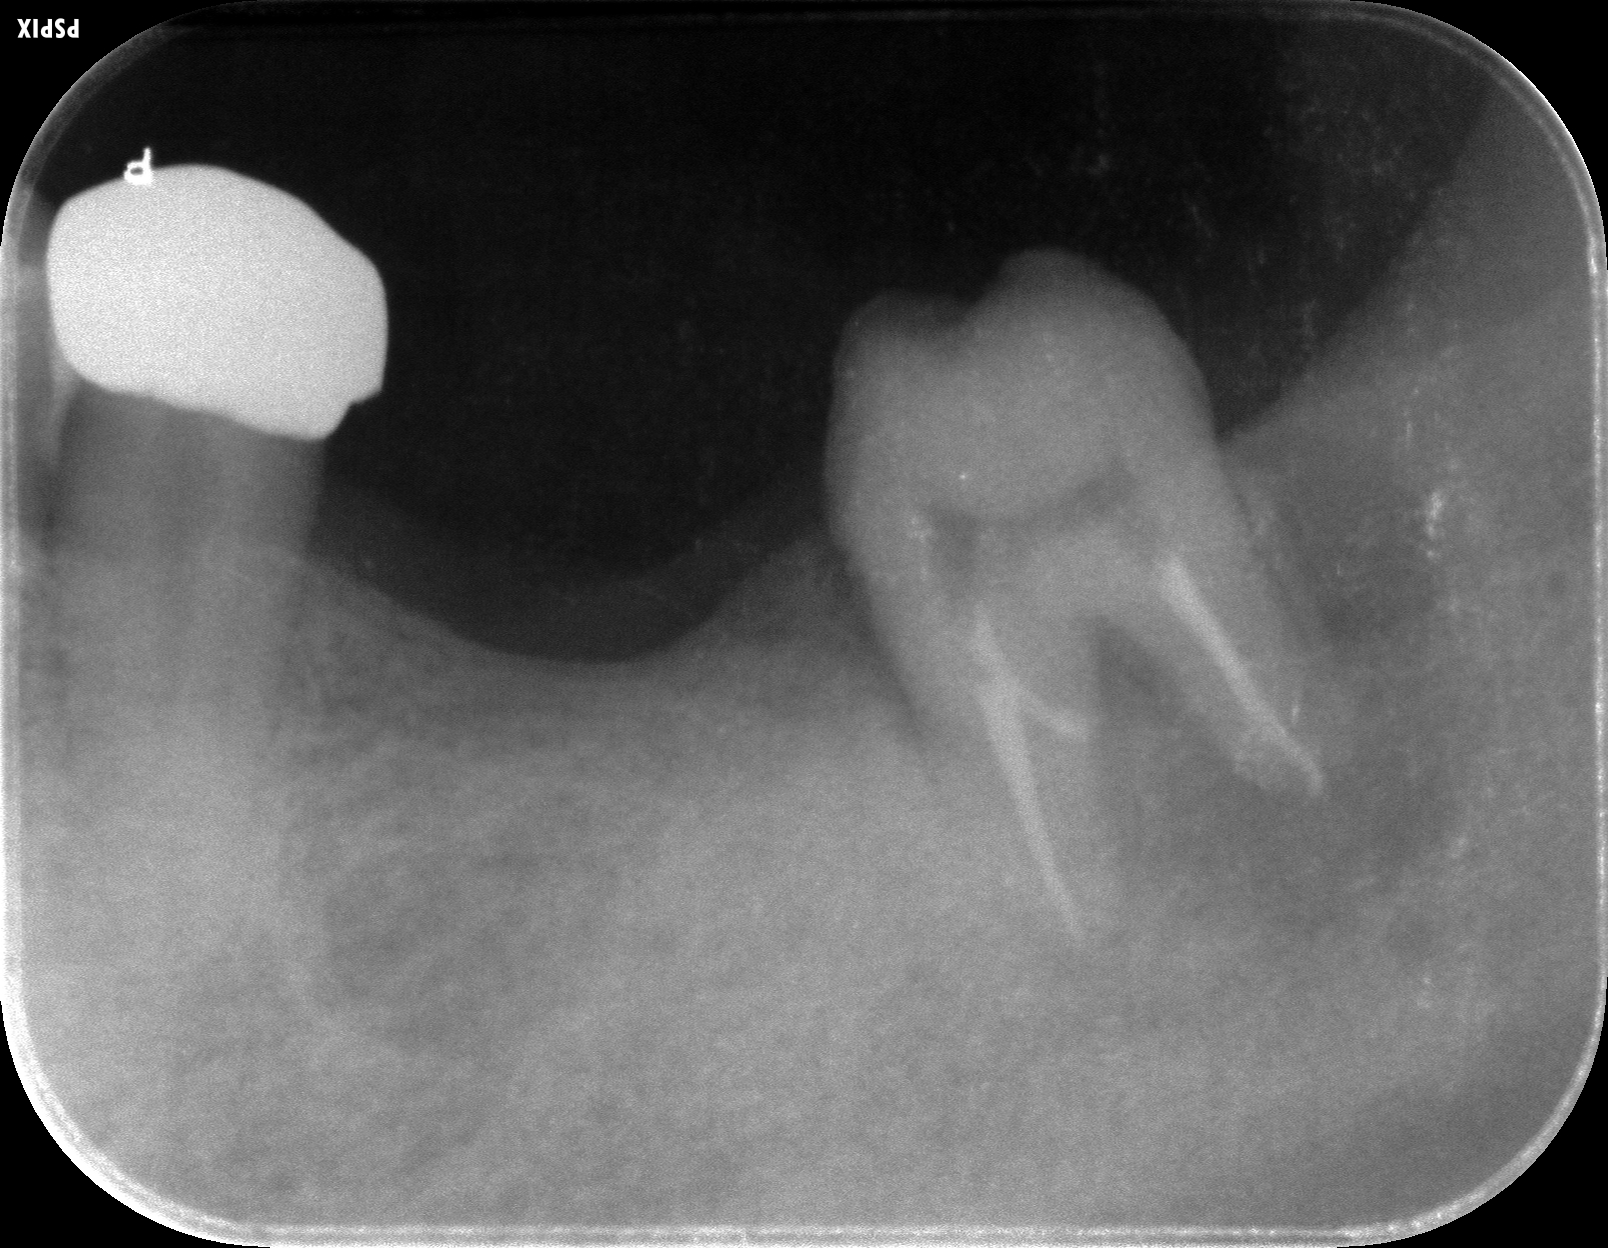

術前のレントゲン写真です。歯の周りに黒い像がありますが骨の吸収像です。